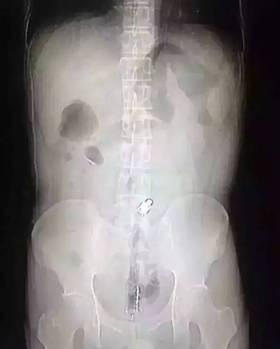

“因为物体边缘比较光滑,手术的时候,我们两个人合作,一个人顺着肚子一点点推,推到肛门口,我把异物拿了出来,大概花了十分钟时间。”郁峰说,这名男子运气算好的,因为根据拍片检查,当时那根振动棒已经挤到了肚脐的部位,情况其实已经相当危险。医生提醒 “那根振动棒有20公分,人的直肠只有18公分,它的长度已经超过直肠了,到达乙状结肠,会引起肠子破裂坏死,如果破了就会有生命危险 。 ”